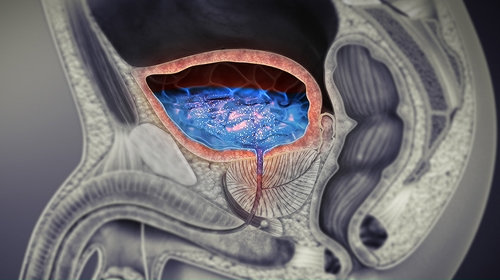

Bệnh tuyến tiền liệt

Bệnh tuyến tiền liệt

Các vấn đề ở tuyến tiền liệt như viêm tuyến tiền liệt, phì đại tuyến tiền liệt… có thể ngăn nước tiểu lại gây viêm, tiểu rắt, tiểu buốt.